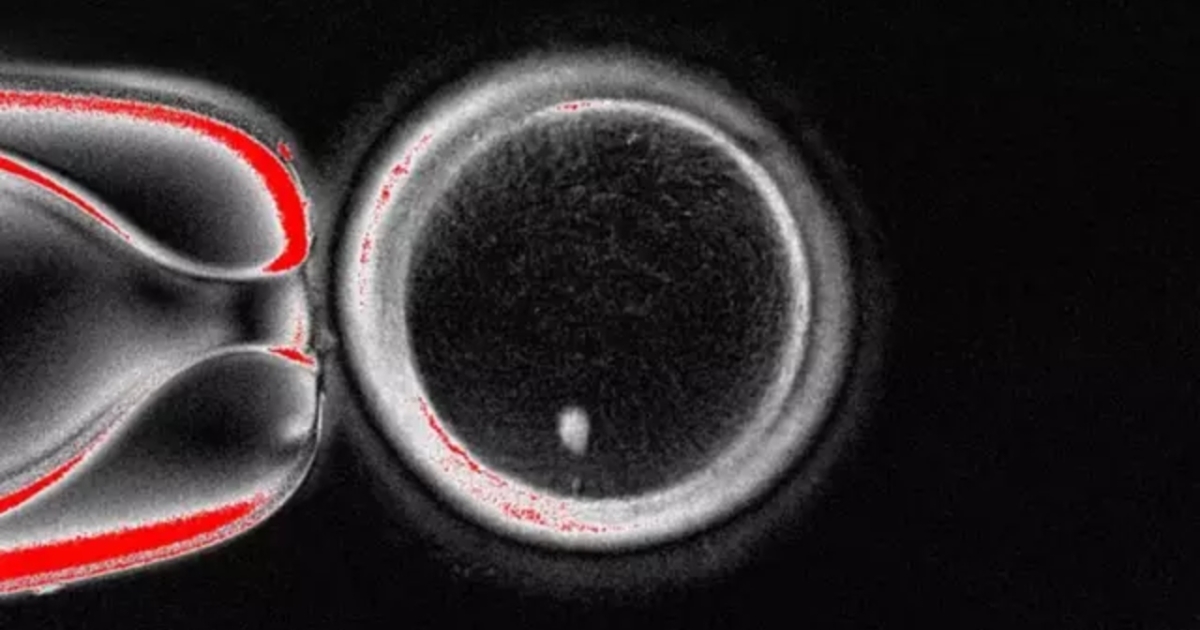

Μια πρωτοποριακή μελέτη άνοιξε τη συζήτηση για το ενδεχόμενο τα μωρά να μπορούν, στο μέλλον, να γεννιούνται χωρίς τη συμβολή βιολογικής μητέρας. Οι επιστήμονες κατάφεραν να δημιουργήσουν κύτταρα που μοιάζουν με ωάρια, χρησιμοποιώντας DNA από απλά κύτταρα του δέρματος. Αυτά τα «τεχνητά ωάρια» μπορούν, θεωρητικά, να γονιμοποιηθούν, γεγονός που ανοίγει νέους δρόμους στην έρευνα της γονιμότητας.

Η επιστήμη της αναπαραγωγής βρίσκεται μπροστά σε επανάσταση: ερευνητές δημιούργησαν ωάρια από δερματικά κύτταρα, ανοίγοντας τον δρόμο σε άνδρες και γυναίκες με υπογονιμότητα να αποκτήσουν βιολογικά παιδιά χωρίς βιολογική μητέρα.